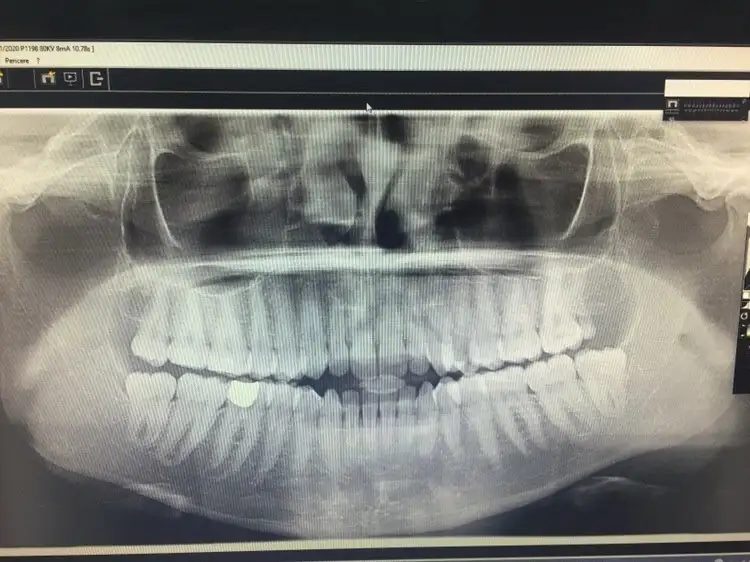

Daha önceki konularımda doktorumdan bahsetmiştim. İzmir'de seyithan kırtaya rinoplasti oldum. 1,5 yıl önce. Her şey çok iyi çok güzeldi ta ki burundaki şişler inip durum farkedilinceye kadar. Doktorum hep ilgili gibiydi tabi ki şikayetlerimi anlatana kadar. Dişimi yaptırmaya gittiğimde röntgen çektiler ve ilk yamukluğu röntgende fark ettim. Columella yamulmuş sol burun deliğimin üstündeki kıkırdak düşmüş. Fotoğrafı ve bazı şikayetlerimi dile getirince doktorum hiç ilgilenmemeye başladı. Sağ deliğin içinde hep ödem olduğunu düşündüğüm bir şişlik vardı meğer ödem değil et parçasıymış. Bundan dolayı sağ delik kapalı nefes alamıyorum yatarken ve rüzgar gibi ses geliyor. Birde septum sağa doğru yamulmuş. Bir burun deliğim geniş büyük biri normal. Sağ burun girişinde bir şişlik var hala geçmedi. Ben bunları dile getirmeye başlayınca melake olan doktor bana sürekli görüldü atmaya cevap vermemeye başladı. Üstüne beni birde engelemiş. Sanki sapasağlam burnumu bu hale ben getirdim. Yani diyeceğim o ki ameliyat olurken iyice araştırın. Doktorlar yaptıkları iyi burunları atıyorlar bunlara sakın aldanmayın. Şimdi burnumun bir tarafı düz iniyor bir tarafı kavisli. Hiç şikayet etmeyince iyisiniz ama yaptığı hataları söyleyince sizden kötüsü yokkk! Bir canla beraber ömür boyu sürecek bir psikolojide teslim ediyorsunuz ama onlar içine edip bırakıyor ve hiçbir şey olmamış gibi hayatlarına devam ediyorlar. Hiç kimsenin gülen yüzüne ilgi gösteren tavırlarına kanmayın. İyice araştırın ve öyle karar verin. Röntgen fotoğrafından burnun bahsettiğim durumuna bakabilirsiniz.

Eki Görüntüle 2653428